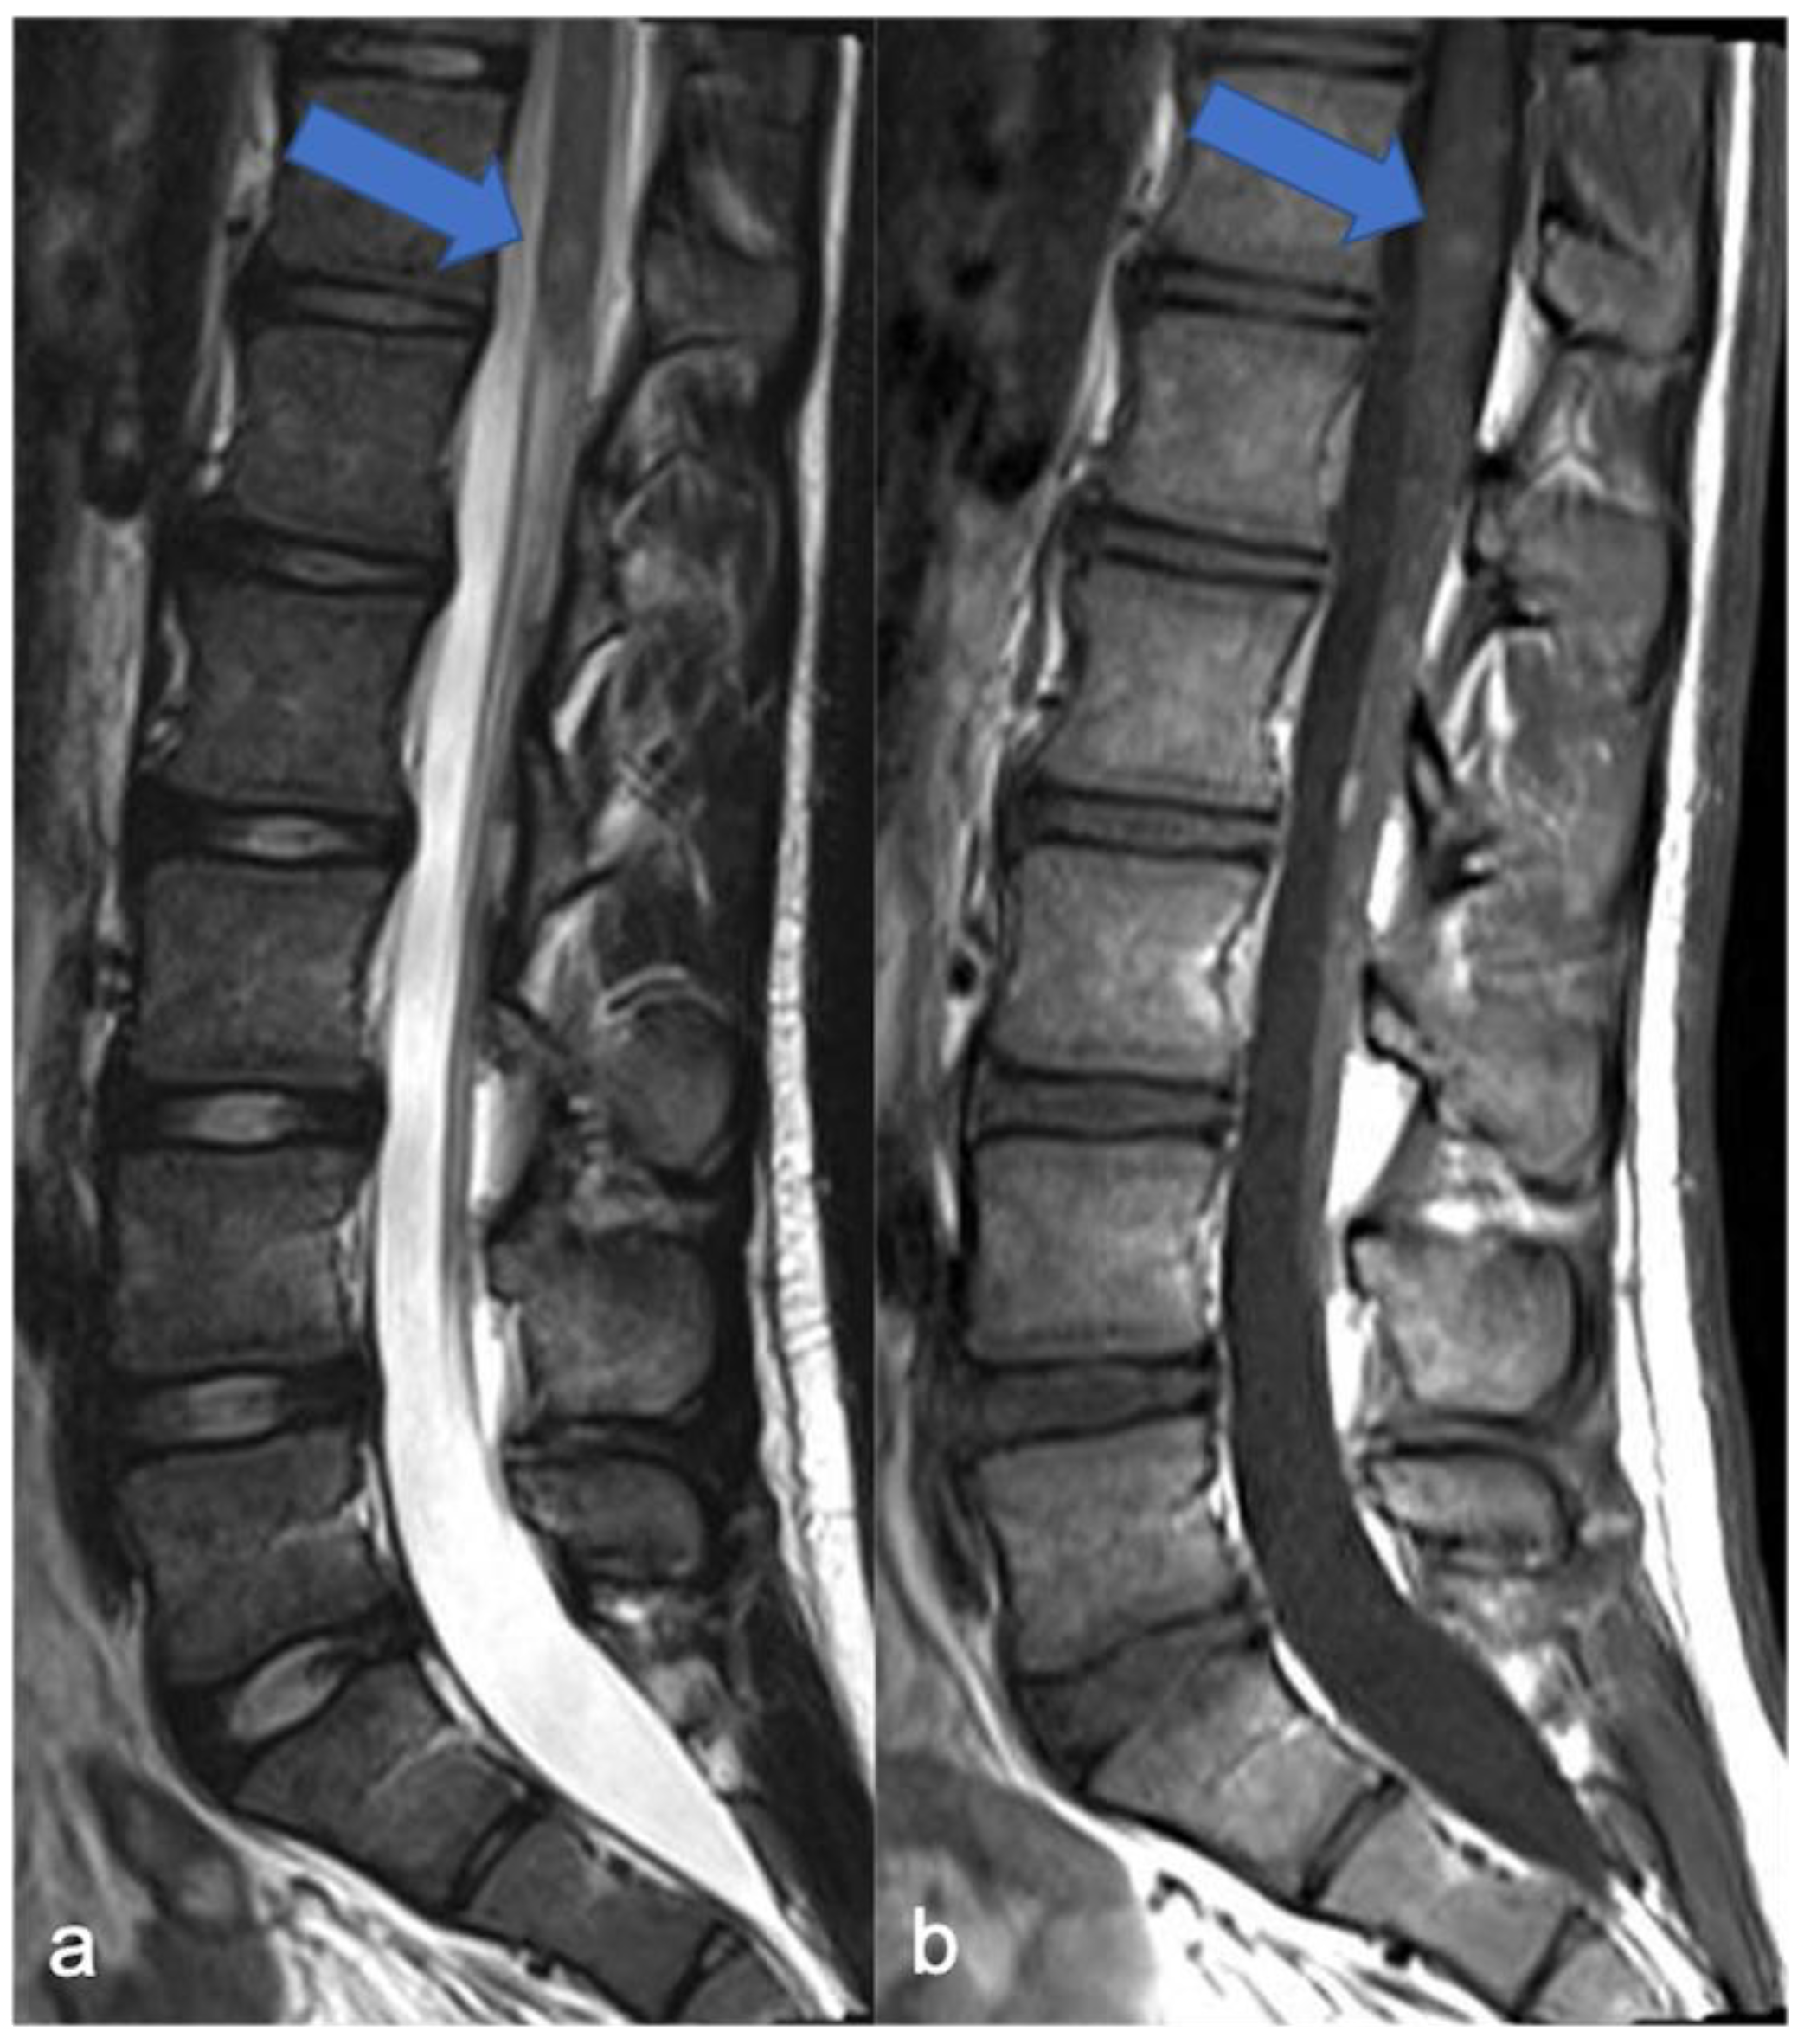

3. Ependymomas